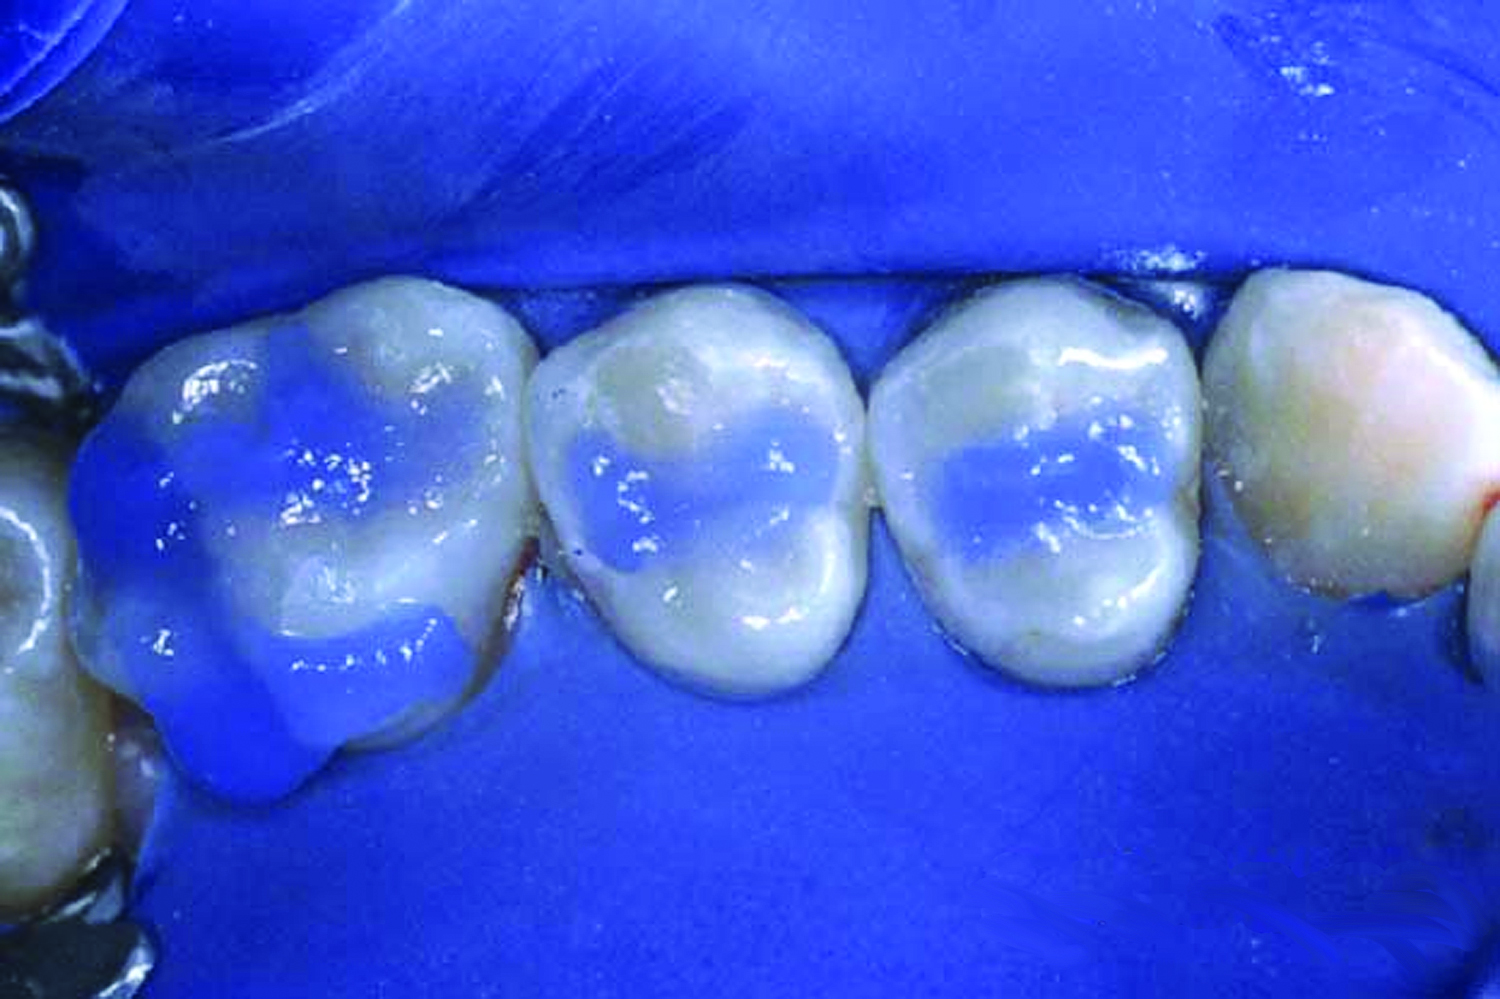

9. Apply the sealant over the pits and fissures (Figure 10). Avoid over manipulation to prevent producing air bubbles. Cover all the pits and fissures, but do not overfill to a high, flat surface.

Fig 11. Once the sealant is polymerized, evaluate the sealant with an explorer and check for a hard, smooth surface and retention.

Figure 11